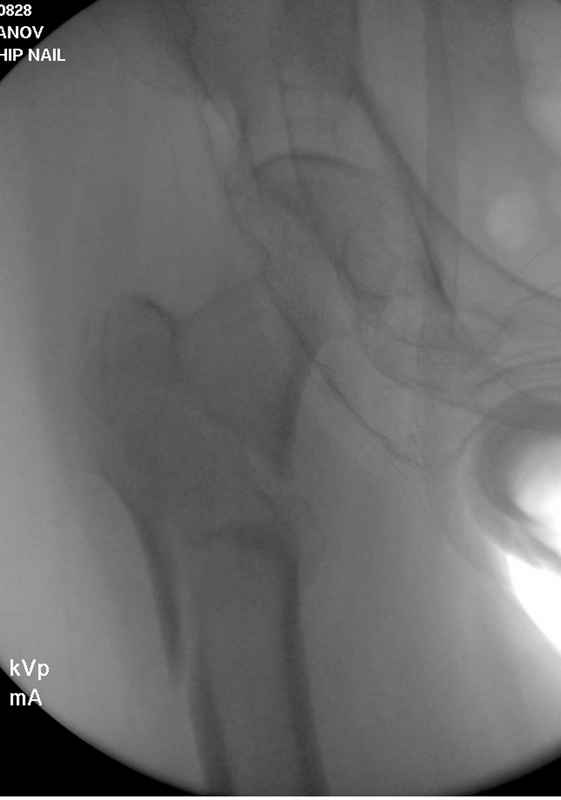

Здесь 83 года, травма в результате падения

судя по картинкам с ЭОПа явно использовались приемы непрямой репозиции под его контролем, а так же интраоперационный ЭОП-контроль положения винтов, без такого контроля операция может ухудшить ситуацию (опять же учтите сроки) т.к. результат буде зависеть в большей степени от искусства хирурга, а не от технологии